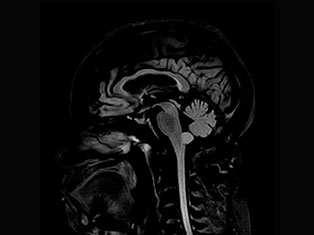

Spinal Tumors

A spinal tumor is a growth that develops within your spinal canal or within the bones of your spine. A spinal cord tumor, also called an intradural tumor, is a spinal tumor that that begins within the spinal cord or the covering.